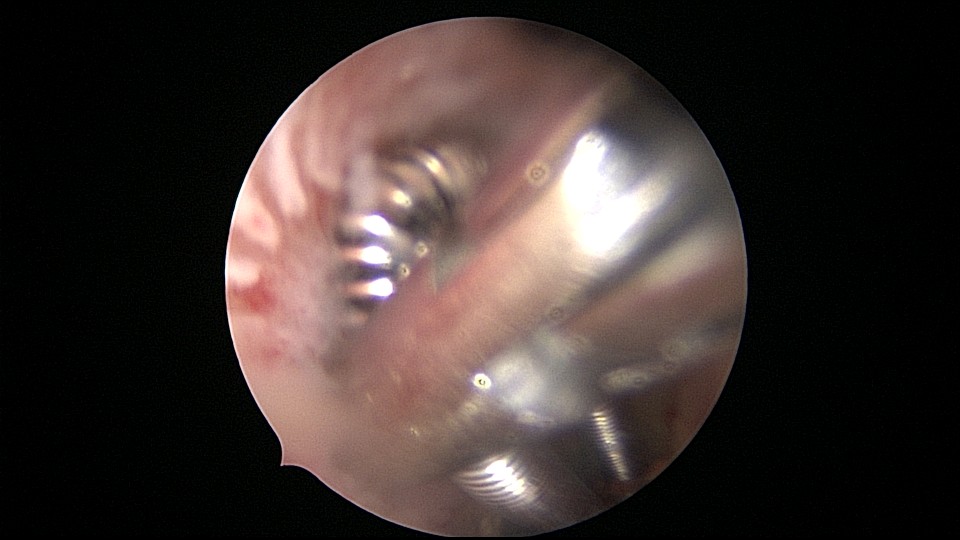

患者28岁,G7P3,顺产3次,完全纵膈子宫,单宫颈。2015年、2018年顺产,2019年左侧宫腔计划外妊娠行宫腔镜取胚及左侧宫腔放置γ环(推测既往妊娠左侧宫腔妊娠可能性大)。2023年4月带环受孕(应该为右侧宫腔妊娠),2023年12月足月阴道分娩,分娩时试图取出左侧宫腔内节育器,因操作困难,取环失败。2024年2月顺产后67天,要求取出宫内节育器,左手臂放置皮埋避孕棒。B超提示环距宫底1.1cm,环两翼分别距子宫前壁浆膜面0.4cm,距子宫后壁浆膜面0.3cm。宫腔镜术中膨宫困难,见宫颈管及宫腔少许淡黄色脓液流出,γ环逆时针旋转约80度,两臂指向左侧宫腔前后壁(2019年放置环时亦如此,因单侧宫腔前后径大于横径所致)。异物钳取出节育环,左右侧宫腔均见散在黄色机化组织,未取病检。